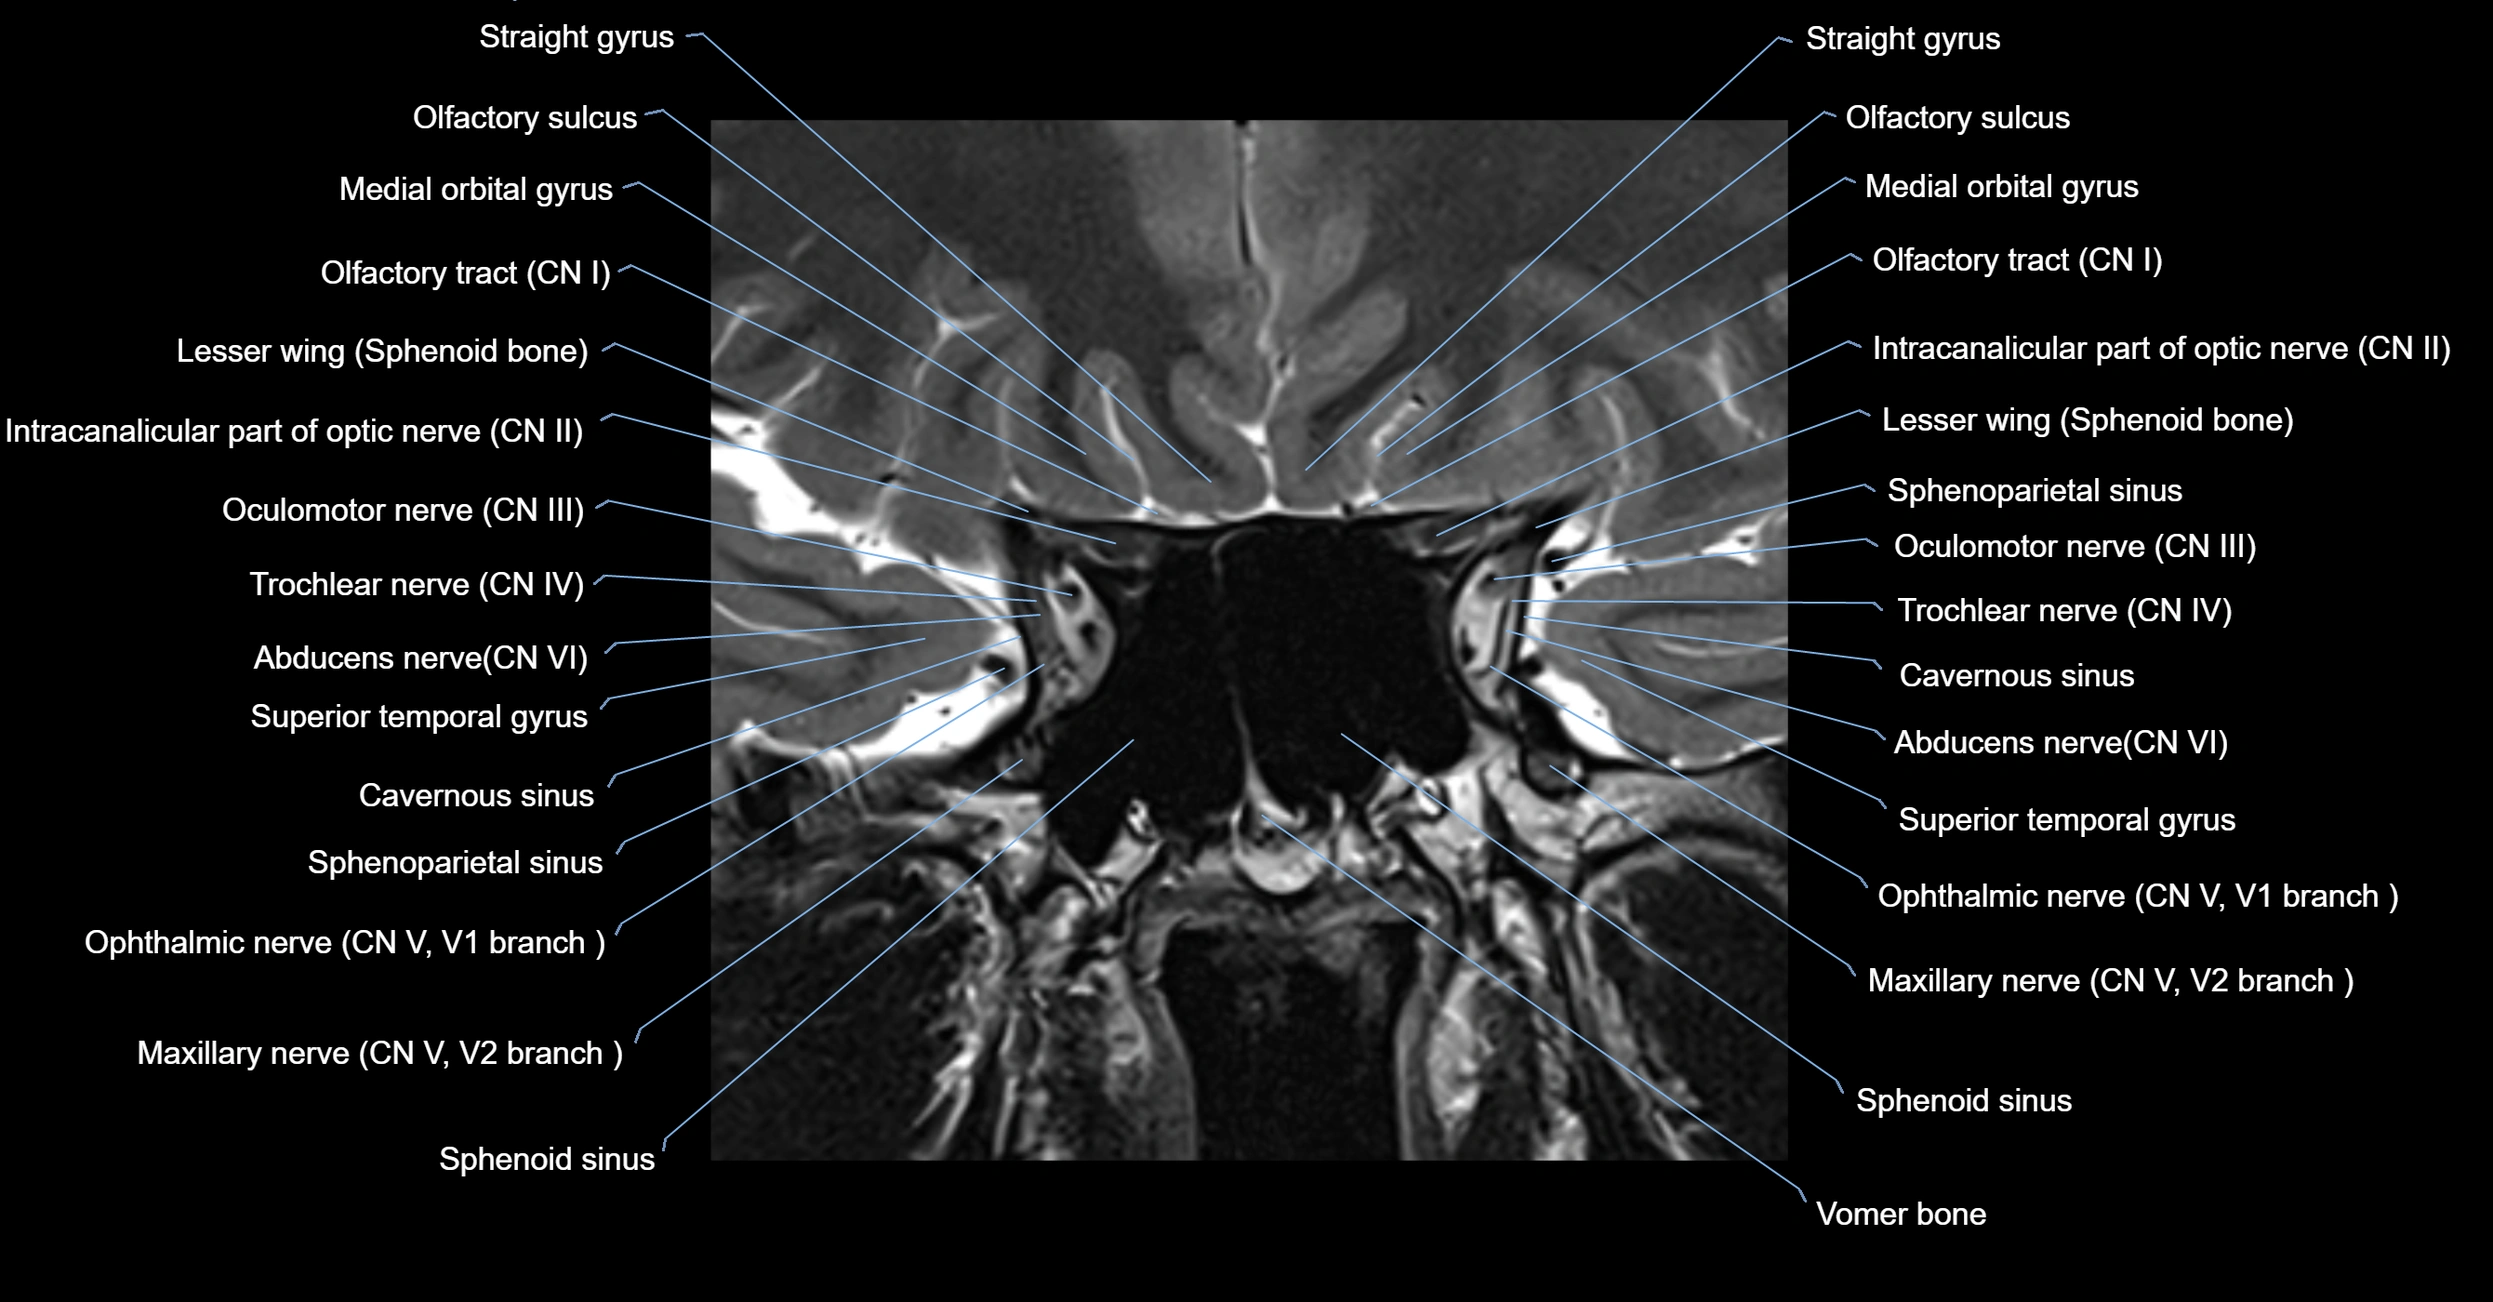

MRI Appearance

The abducens nerve is a small, thin, linear structure

Best visualized on high-resolution T2-weighted 3D MRI sequences (e.g., FIESTA or CISS)

Seen as a hypointense (dark) line running from the brainstem at the pontomedullary junction, traversing the prepontine cistern, and entering Dorello’s canal under the petrosphenoidal ligament, then into the cavernous sinus, and finally the orbit

May be challenging to visualize in standard MRI due to its small size

Pathology may be inferred by absence, displacement, or enhancement of the nerve

MRI images